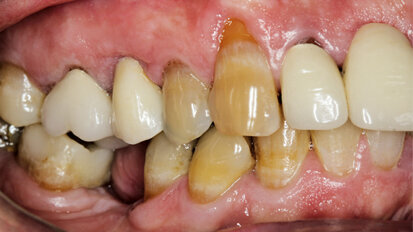

Rehabilitace Straumann